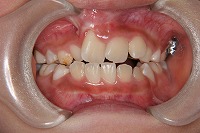

反対咬合を主訴に来院された、右側唇顎裂の10歳6ヵ月の女の子です。診断「右側唇顎口蓋裂で反対咬合を伴う」1期治療で反対咬合の解消と上顎の前歯の並びを修正しました。2期治療は抜歯をせず治療を行いました。